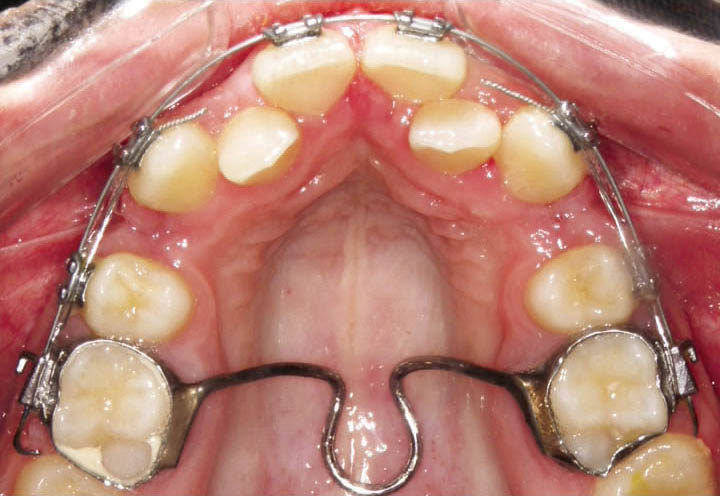

اگر نیاز به ساختن لینگوال آرچ یا پالاتالبار دارید (مثلاً برای جلوگیری از حرکت مزیالی مولرها و حفظ فضای E) باید بندها را در جایگاه خود بگذارید و با گیج ارتفاع آن را تنظیم کنید، بعد یک قالب pick-up از روی آنها با آلژینات میگیرید. سپس بندها را خارج و درون آلژینات میگذاریم (شکل 60-1) و گچ آن را میریزیم. بدینصورت بندها به روی کست گچی منتقل میشوند. حال این قالب را به لابراتوار بفرستید تا پالاتالبار یا لینگوال آرچ بسازند. بهتر است بندها را یک درجه بزرگتر بگیرید تا زمانی که به یکدیگر لحیم میشوند جازدن روی دندانها مشکل نشود.

شکل 60-1: قالب pick-up از بندها جهت ساخت لینگوال آرچ و پالاتال بار

برای ساختن پالاتالبار (شکل 61-1) بهتر است از سیم 1.2mm استفاده نمائید ولی برای ساختن لینگوال آرچ (شکل 62-1) سیم 1mm هم کافی میباشد. این سیم بندهای مولراول را بههم متصل میکند و دارای لوپی هستند که انعطاف پذیری آن را بیشتر میکند.

شکل 61-1: پالاتال بار